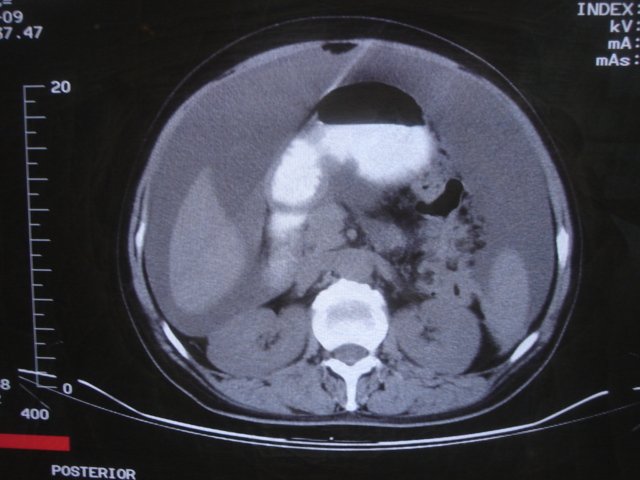

患者 女 52 腹部大量腹水。大家帮忙看看胃窦部有问题吗?

b超显示腹部、盆腔未见异常;化验室检查afp cea 正常,ca125 升高 347.4。

腹部大量腹水。胃窦部胃壁增厚,轮廓不规则!

1)不排除胃癌可能;建议行胃镜检查。2)大量腹水。

网膜不干净,可能为癌性腹膜炎。

胃窦部及小弯侧壁限局性增厚,胃癌待除外。建议胃镜检查!

腹部大量腹水。胃窦部胃壁增厚,轮廓不规则,胃癌待除外,建议胃镜检查。